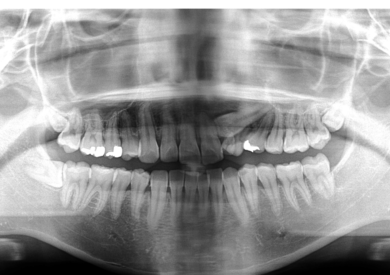

永久歯(左上の犬歯)が顎の骨の中で正しい方向に成長せず埋まったままになっていました。(埋伏歯)

また左上の中央から2番目の歯は生まれつき存在しませんでした。(先天性欠如)

永久歯2本分の場所に、大人になるまで乳歯が残ってしまった症例です。